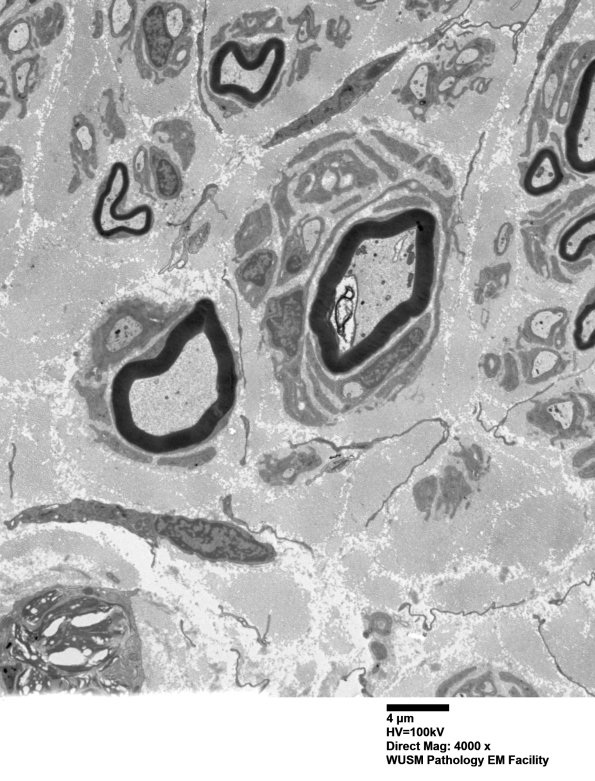

Pseudo-Onion bulbs frequently are composed of non-contiguous sectors of Schwann cell processes. (electron micrograph)